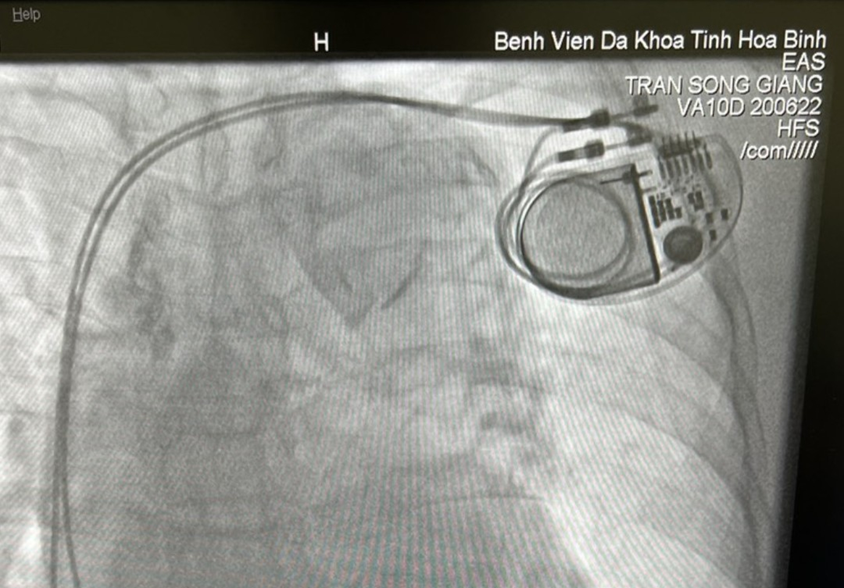

Các chuyên gia Bệnh viện Bạch Mai phối hợp thực hiện và chuyển giao kỹ thuật cấy máy tạo nhịp tim vĩnh viễn hai buồng, giúp người bệnh vượt qua cơn nguy kịch

Tại buổi chuyển giao, các chuyên gia về đặt máy tạo nhịp tim của Viện tim mạch Quốc Gia, Bệnh viện Bạch Mai đã trực tiếp tập huấn, chuyển giao kỹ thuật tại chỗ, hỗ trợ cán bộ kỹ thuật của Bệnh viện Đa khoa tỉnh cập nhật các kỹ thuật đặt máy tạo nhịp. Đồng thời, phối hợp thực hiện cấy máy tạo nhịp tim vĩnh viễn cho bệnh nhân B.T.N được chẩn đoán là suy nút xoang có rối loạn nhịp chậm nguy hiểm có khoảng ngừng tim dài. Sau cấy máy tạo nhịp tim vĩnh viễn hai buồng, bệnh nhân qua cơn nguy kịch và sức khỏe phục hồi tốt. Thông qua các kỹ thuật này giúp các Bác sỹ khoa Nội tim mạch xử trí cấp cứu các bệnh nhân rối loạn nhịp tim nguy hiểm bằng kỹ thuật cao hiện đại, giúp bệnh nhân nhanh chóng ổn định và an toàn.